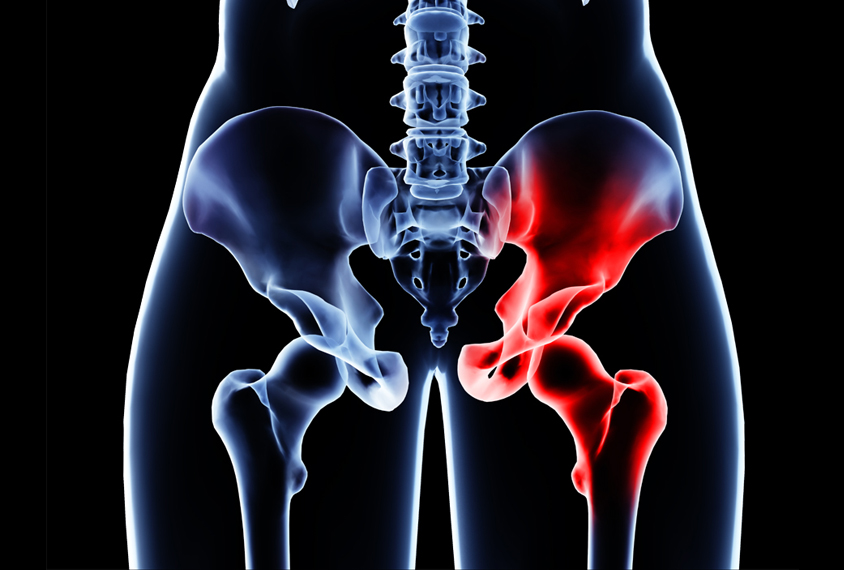

고관절 통증 증상(엉덩관절)은 오른쪽과 왼쪽의 골반과 넙다리뼈가 연결된 관절의 통증을 일컫습니다. 고관절은 상체의 하중을 분산시키는 역할을 하며, 일어서거나 앉거나 일상생활에서 자주 쓰이는 관절이며 부담도 잘 받게 됩니다. 모양도 크기도 탁구공만 합니다. 일상적으로 걸을 때 고관절에 체중의 3~4.5배의 무게가 실리게 됩니다. 계단을 오를 때는 대퇴골두에 전해지는 무게는 몸무게의 8배, 달리는 경우 10배에 가까운 하중을 견뎌내애 한다고 합니다. 탁구공 크기만 한 대퇴골두가 감당하기에는 너무 무겁기 때문에 고관절이 느끼는 부담도 크고 쉽게 손상될 수 있습니다. 다른 관절과 마찬가지로 감당하기 어려운 충격이나 무게가 가해지면 고관절 통증 증상이 발생하게 되는데요. 퇴행성 고관절염, 대퇴골 골절, 대퇴골두 무혈성 괴사, 선천성 고관절 탈구 등이 대표적인 고관절 통증 질환입니다.

나쁜 자세 또한 고관절 통증을 일으키게 되는데 자세로 인한 통증은 주로 한쪽에 나타납니다. 한쪽에 체중이 실리면 그쪽 고관절이 아플 수 있으니 다리꼬기, 짝다리 짚기, 비딱하게 앉기 등을 주의하셔야 합니다.. 책상다리 또는 양반다리라고 하는 자세도 삼가하는 것이 좋습니다.